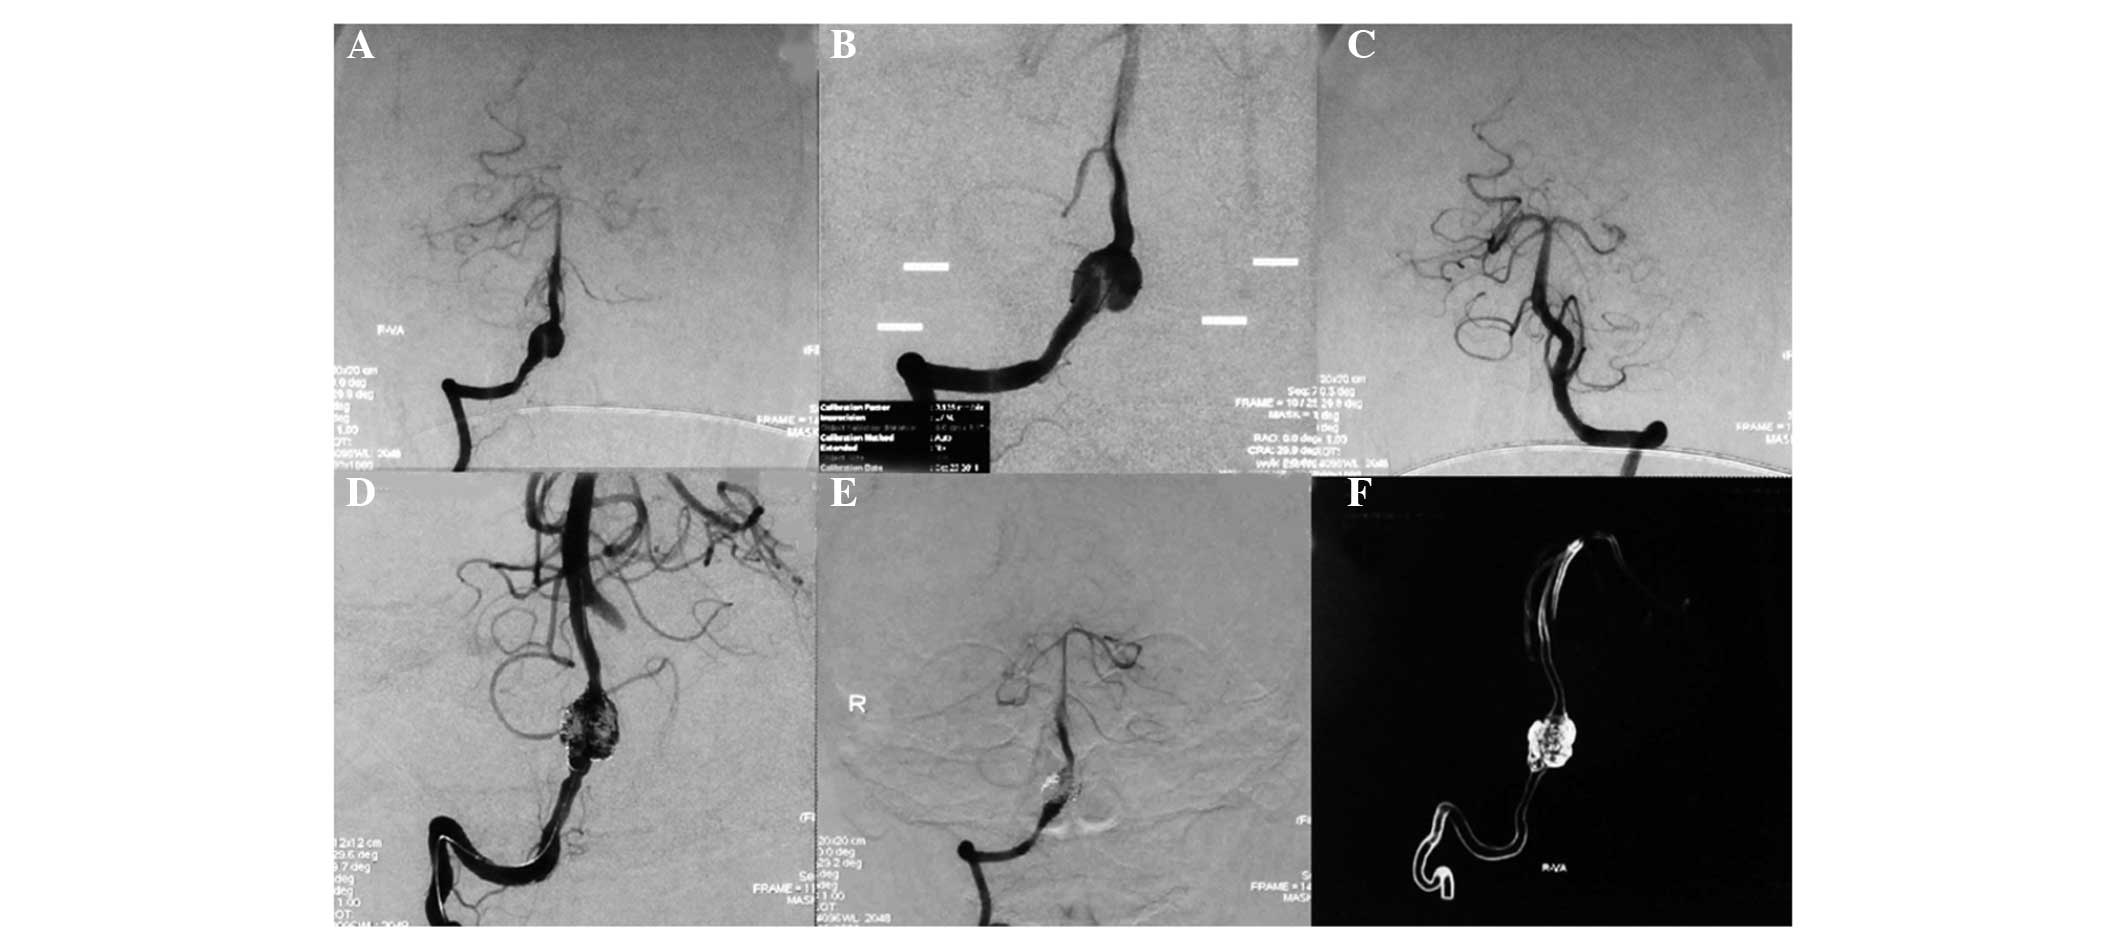

Among the 10 patients with type I aneurysms, four patients with type Ia received coiling with parent artery occlusion (Fig. 1), one patient with type Ia received stent-assisted coiling, three patients with type Ib received stent-assisted coiling (Fig. 2), one patient with type Ib received coiling only and one patient with type Ib was treated conservatively. Among the 13 patients with type II aneurysms, two patients with type IIa received coiling with parent artery occlusion (Fig. 3), five patients with type IIa received stent-assisted coiling (Fig. 4) and all six patients with type IIb received stent-assisted coiling. Among the eight patients with type III aneurysms, four patients with type IIIa received coiling with parent artery occlusion (Fig. 5), one patient with type IIIa received stent-assisted coiling (Fig. 6), two patients with type IIIb received stent-assisted coiling and one patient with type IIIb received coiling only.

Figure 6

(A) Digital subtraction angiography (DSA) and (B) amplified DSA images showing a well-developed type IIIa dissecting aneurysm of the right vertebral artery located proximally to the posterior inferior cerebellar artery and the contralateral vertebral artery. DSA images showing the (C) left vertebral artery and (D) stent-assisted coiling treatment of the right vertebral dissecting aneurysm. The post-treatment angiograms show (E) complete obliteration of the aneurysm and (F) that the right vertebral artery was filled well.